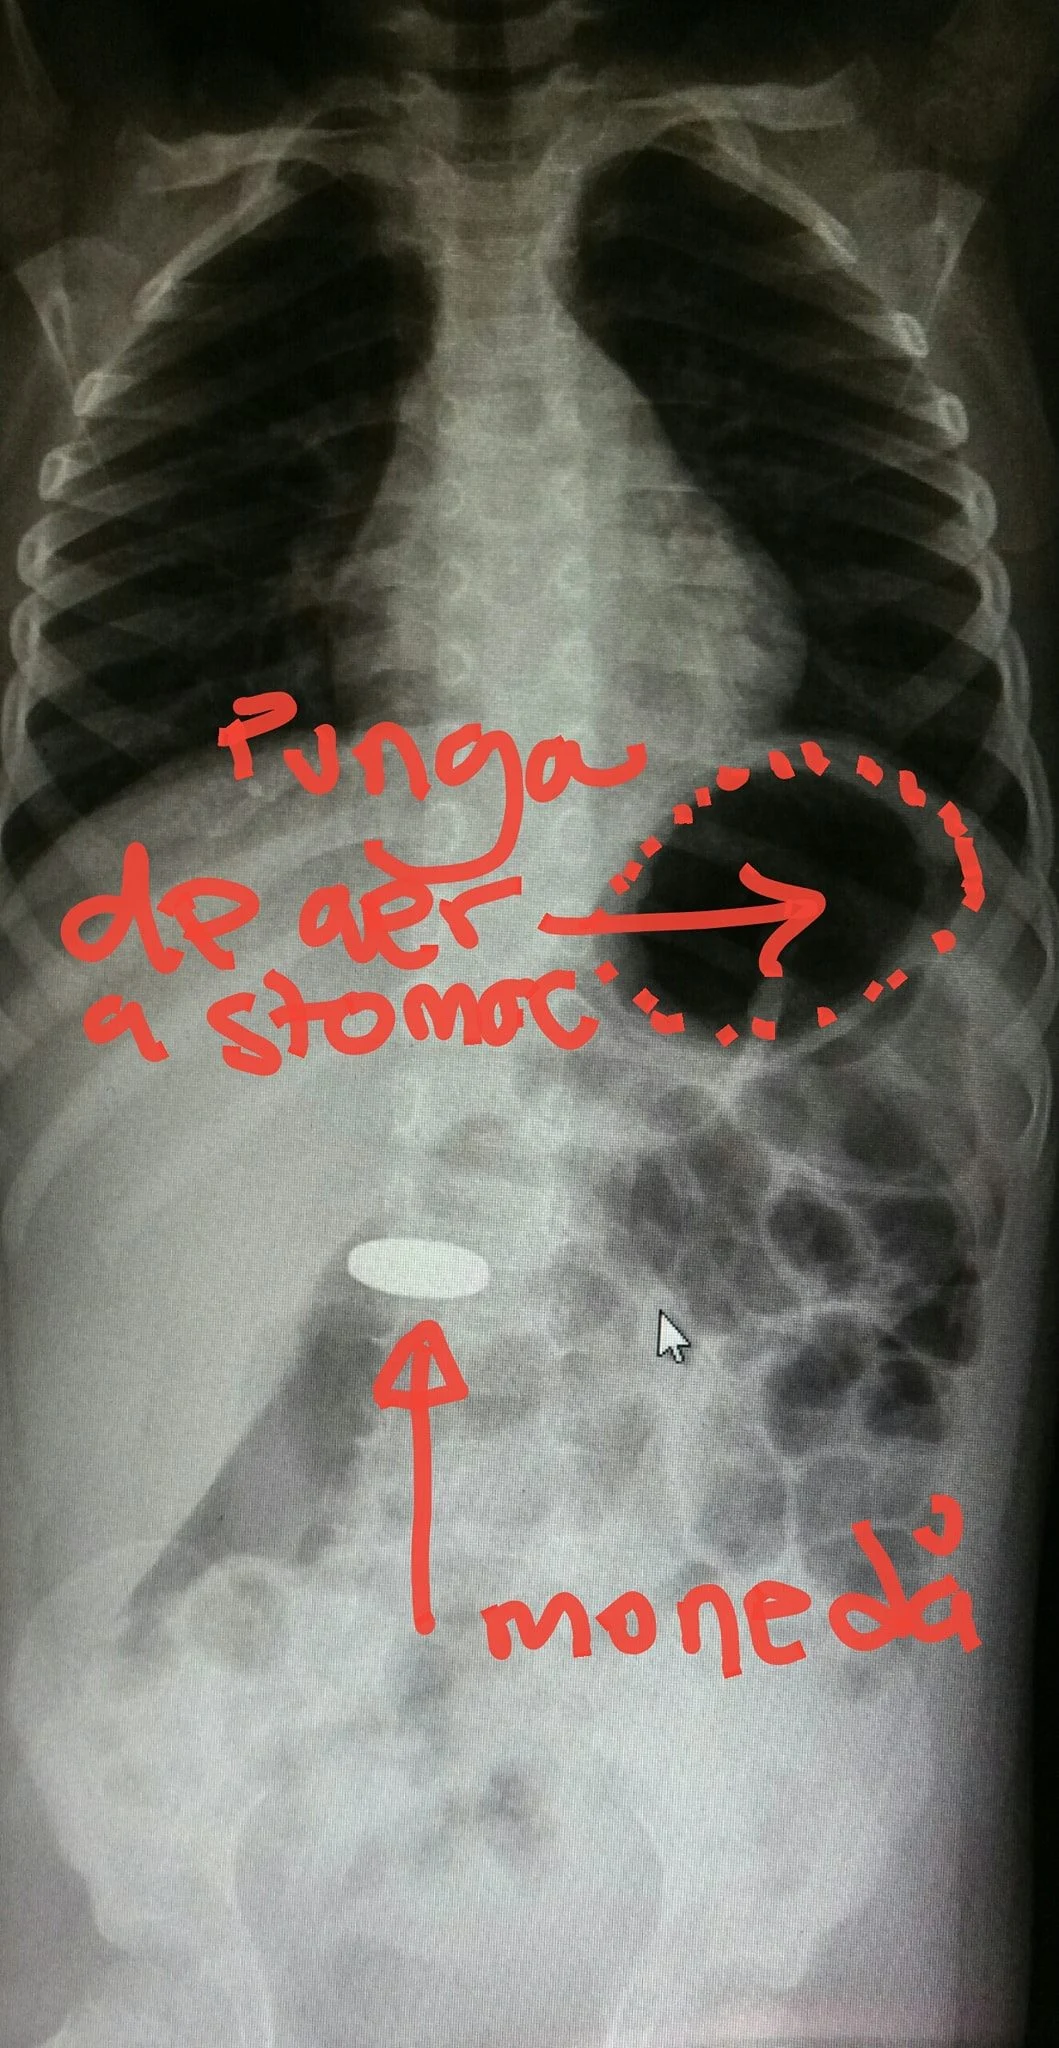

„Dacă este un corp metalic mic (o monedă de 50 de bani în cazul acestui pacient din imagine) este extrem de puțin probabil să apară efecte adverse şi acesta se va elimina prin materiile fecale după ce a parcurs încet (în 2-3 zile) tot tubul digestiv”, mai spune el.

„Periculoşi sunt acei corpi străini care rămân blocați, pentru că sunt prea mari (mai lungi de 6 cm şi cu grosime mai mare de 2 cm) sau au margini tăietoare sau înțepătoare sau conțin material coroziv (cum sunt bateriile). Daca un corp străin trece de esofag şi ajunge în stomac (în poza se vede că moneda este mai jos decât punga de aer a stomacului) acesta va ieşi singur, de obicei”, mai arată el.

„Diagnosticul de certitudine, pentru a lua cea mai buna decizie de tratament, îl pune radiografia abdominală „pe gol” (adica făra substanța de contrast) cu pacientul stând în picioare, pentru corpii radioopaci. Rareori e necesara endoscopia pentru a extrage corpii blocați sau tăietori/înțepători sau baterii alcaline”, mai spune el.